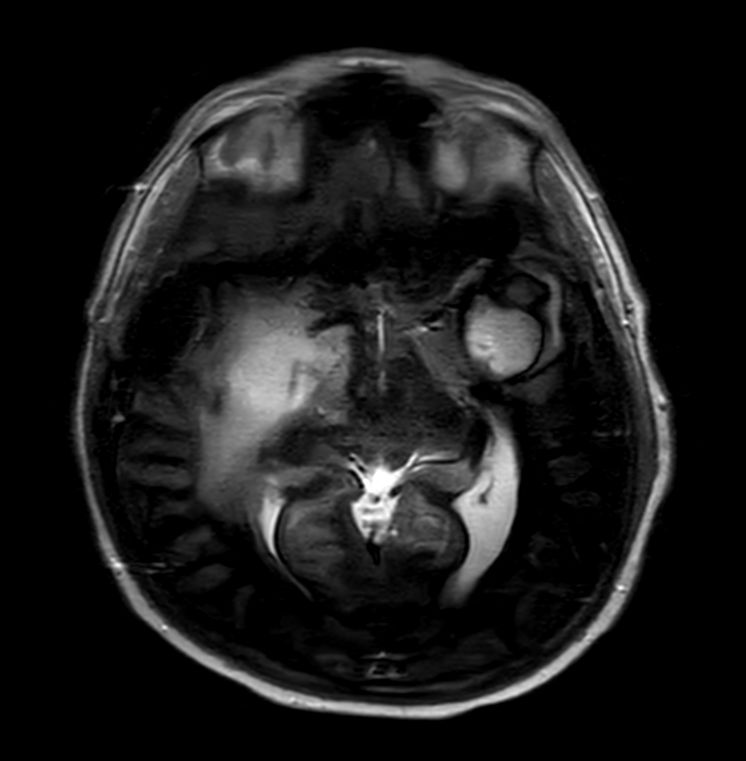

Patient with a large brain lesion. AI based SmartSpeed is utlized to shorten scan time without compromise in image quality. Advanced imaging techniques like pCASL and 3D APT are used to perform contrast-free brain imaging to assess perfusion and tumoral activity. SWIp 3D susceptibility weighted offers the high sensitivity required to visualize deoxygenated (venous) blood or calcium deposits. A single synthetic (SyntAc) brain quantification scan is added. The resulting data of this scan can be used as input for advanced third party processing software* to synthesize MR images with different contrasts, brain parenchyma fraction maps and/or brain segmentation maps.

Axial T2w TSE Motion-Free